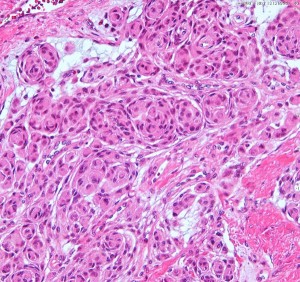

Fibrous meningiomaですが、渦巻状(whorl, long arrow) patternや玉ねぎ茎状 (onion bulb, short arrow) patternなどが見られます。HE x200